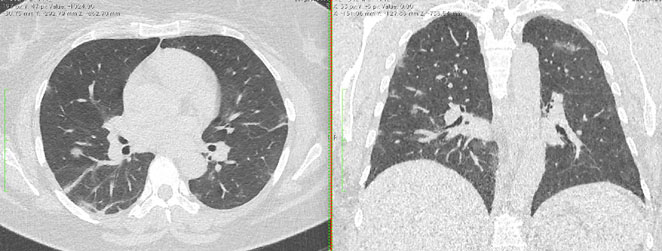

4.3. ЛУЧЕВАЯ ДИАГНОСТИКА COVID-19

Методы лучевой диагностики применяют для выявления COVID-19 пневмоний, их осложнений, дифференциальной диагностики с другими заболеваниями легких, а также для определения степени выраженности и динамики изменений, оценки эффективности проводимой терапии.

К методам лучевой диагностики патологии ОГК пациентов с предполагаемой/установленной COVID-19 пневмонией относят:

- Компьютерную томографию легких (КТ),

КТ имеет высокую чувствительность в выявлении изменений в легких, характерных для COVID-19. Применение КТ целесообразно для первичной оценки состояния ОГК у пациентов с тяжелыми прогрессирующими формами заболевания, а также для дифференциальной диагностики выявленных изменений и оценки динамики процесса. КТ позволяет выявить характерные изменения в легких у пациентов с COVID-19 еще до появления положительных лабораторных тестов на инфекцию с помощью МАНК. В то же время, КТ выявляет изменения легких у значительного числа пациентов с бессимптомной и легкой формами заболевания, которым не требуется госпитализация. Результаты КТ в этих случаях не влияют на тактику лечения и прогноз заболевания при наличии лабораторного подтверждения COVID-19. Поэтому массовое применение КТ для скрининга асимптомных и легких форм болезни не рекомендуется.

15. Рекомендации по формированию описаний и оценке изменений в легких и ОГК при имеющейся/подозреваемой пневмонии COVID-19 представлены в Приложении 1.